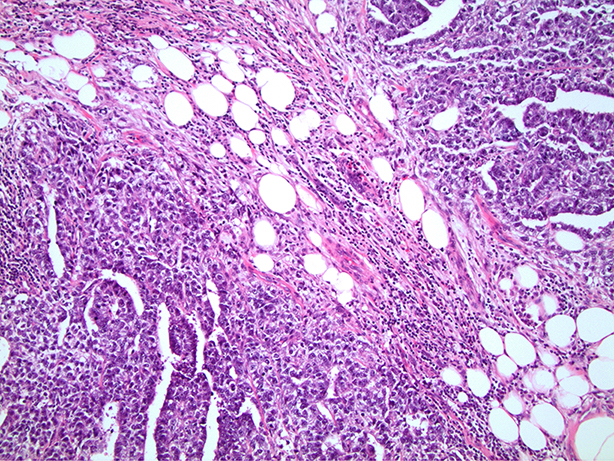

Microscopic (histologic) images

Board review style question #1

In a postpubertal testicular germ cell tumor, lymphovascular (shown above), hilar fat, epididymal and tunica vaginalis invasion are all a part of which pT category?

Board review style answer #1

D. pT2. Lymphovascular, hilar fat, epididymal and tunica vaginalis invasion are all a part of the pT2 category for testicular germ cell tumors. Lymphovascular invasion by embryonal carcinoma is shown in the image.

Comment Here Reference: